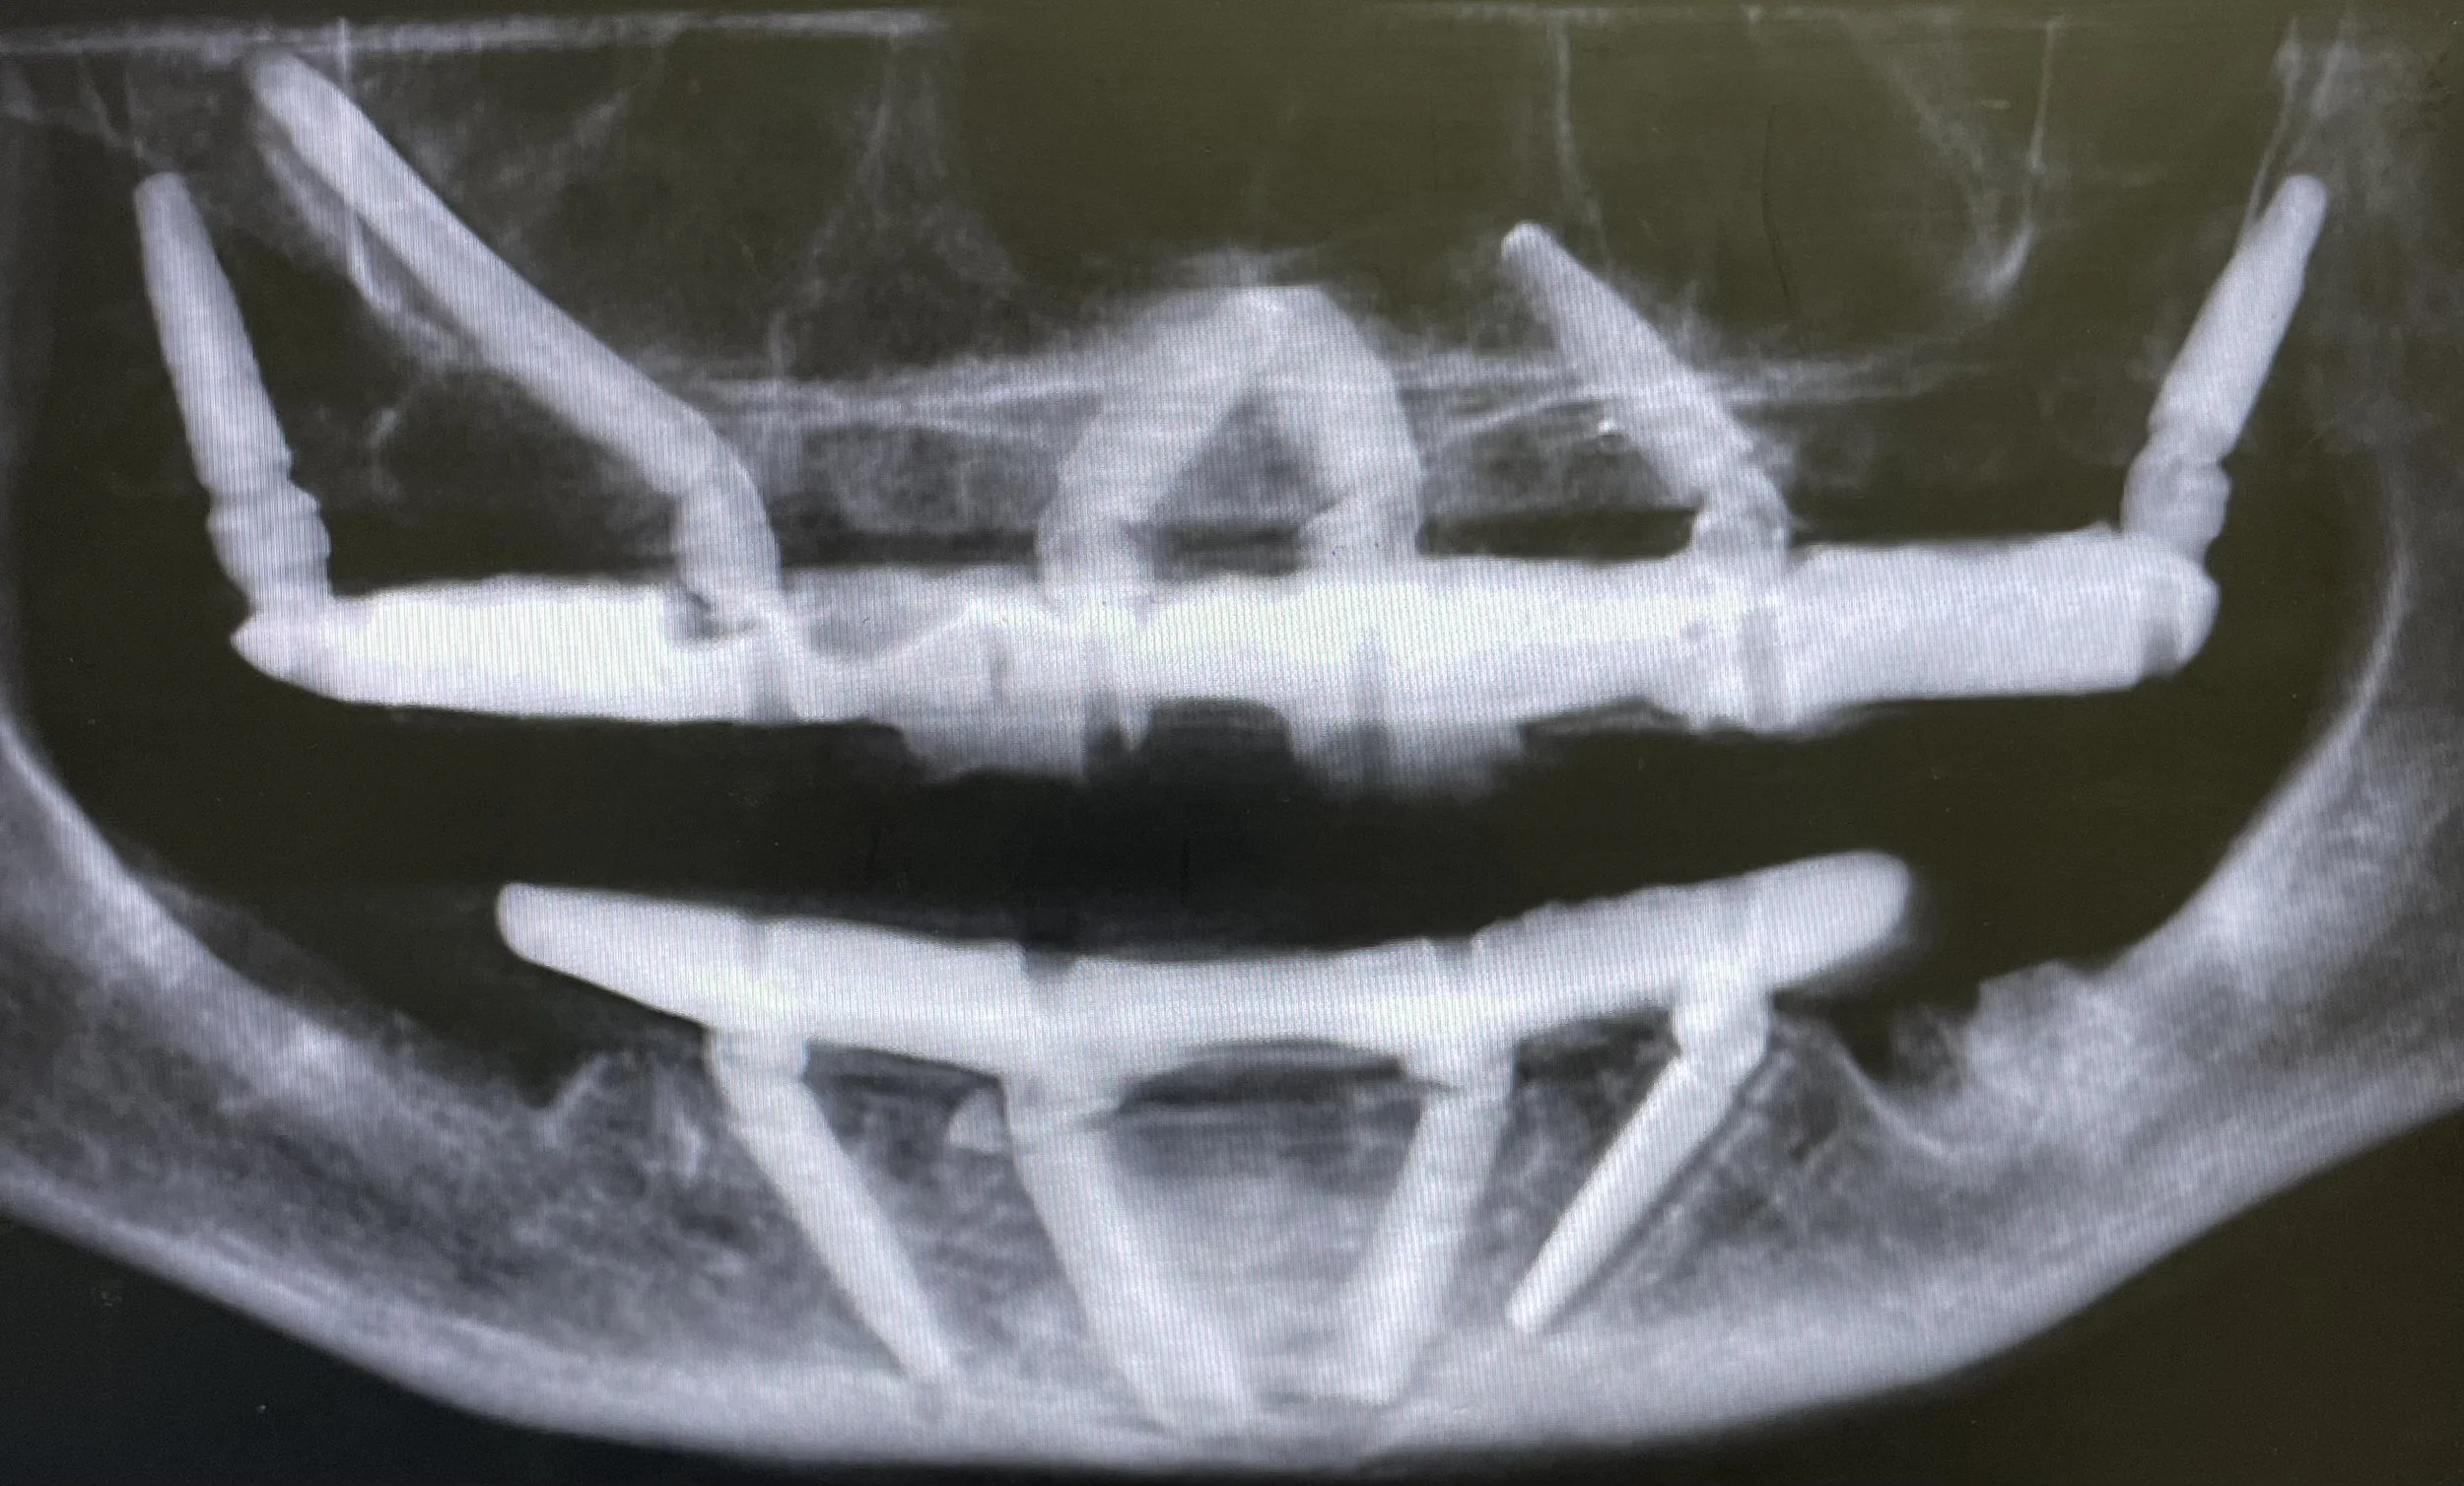

Dr. Damons Cases